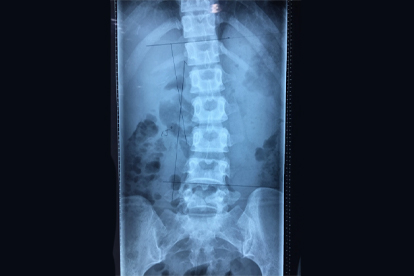

腰椎管狹窄微創(chuàng )手術(shù)后要注意什么

腰椎管狹窄微創(chuàng )手術(shù)后需注意傷口護理、體位管理、康復訓練、藥物使用及定期復查。術(shù)后恢復期可能伴隨疼痛或活動(dòng)受限,需嚴格遵循醫囑進(jìn)行干預。